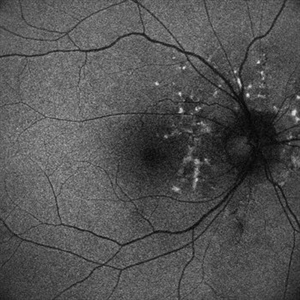

Fundus Autofluorescence Showing Angioid Streaks with Regressing CNV s/p AntiVEGF Injections (RE)

Sep 20 2024 by Anand Temkar

A 45 year old male came to our OPD with chief complaints of DOV in BE since 2 months and wavy vision in periphery. Patient was diagnosed with (BE) CNVM in a case of Angioid Streaks and has already received (BE) bevacizumab x 2.

Photographer: Dr.Anand Temkar- Retina Foundation, Ahmedabad

Imaging device: Mirante

Condition/keywords: Angioid Streaks, choroidal neovascularization (CNV), fundus autofluorescence (FAF)